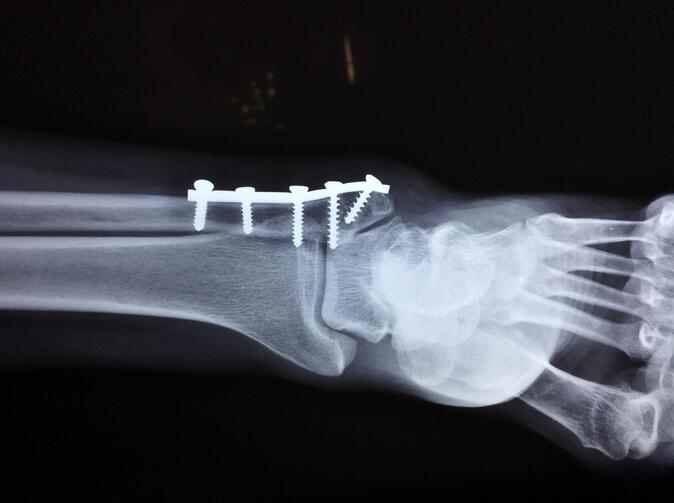

Původní myšlenka denního odškodného úrazem spočívala ve výplatě denní dávky za každý den léčení úrazu. Výhoda má spočívat v tom, že nárok na peníze nevzniká ve spojitosti s pracovní neschopností. Pojištěný může např. se zlomenou nohou „chodit“ do práce a zároveň dostává peníze od pojišťovny. O pojistné události a počtu dnů plnění tak nerozhoduje vystavená pracovní neschopenka, ale lékařské zprávy. V nich je uvedeno datum úrazu a také datum poslední kontroly. V jednoduchých případech tak lze snadno určit dobu léčení. Život je ale složitější a po ukončení léčení na chirurgii může následovat rehabilitace k rozhýbání zatuhlého kotníku. Doba léčení tak přestává být exaktní veličinou a může být výrazně delší. Tuto skutečnost vyřešili pojišťovny zavedením tabulky diagnóz jednotlivých tělesných poškození a přiřazení maximálního počtu plněných dnů.